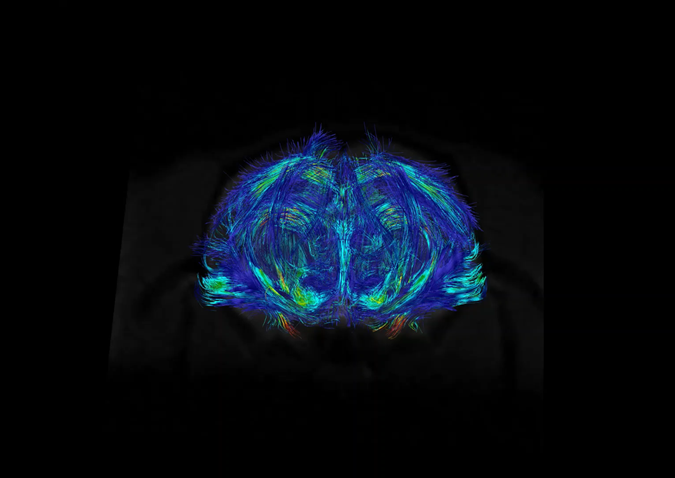

Boğaziçi Üniversitesi Hedefli Tedavi Teknolojileri Merkezi (Boğaziçi CT3) Deney Hayvanları Görüntüleme Birimi, Türkiye’nin ilk preklinik (deney hayvanlarında kullanım için özelleşmiş) 7T MRG (manyetik rezonans görüntüleme) cihazının yanı sıra preklinik BT (bilgisayarlı tomografi) ve hem MRG hem de BT tarayıcıları ile entegre edilerek PET-MRG ve PET-BT çalışmalarına olanak tanıyan PET tarayıcısı ile araştırmacılara ve sektördeki kuruluşlara eşsiz bir altyapı sunmaktadır.

Birimimizde; tüm vücut ve bölgesel MR taramaları, doku karakterizasyonu, metabolik görüntüleme, moleküler hedeflerin izlenmesi ve farmakokinetik değerlendirmeler gerçekleştirilebilmektedir. Ayrıca hayvan kabul ve karantina alanlarımız, uluslararası etik standartlara uygun olarak yapılandırılmıştır.

Yüksek alan kuvveti sayesinde sağlanan üstün görüntü kalitesi ve hassasiyet, özellikle onkoloji, nörobilim, kardiyovasküler ve farmasötik araştırmalarda büyük avantajlar sağlamaktadır. Araştırmalarınıza özgü deneysel protokoller geliştirme, planlama ve analiz süreçlerinde, deneyimli teknik ekibimizle kapsamlı destek sunuyoruz.